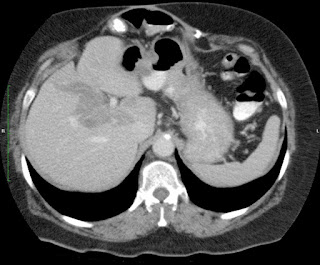

Paciente de 66 años con antecedente de pancreatitis, tomografía control.